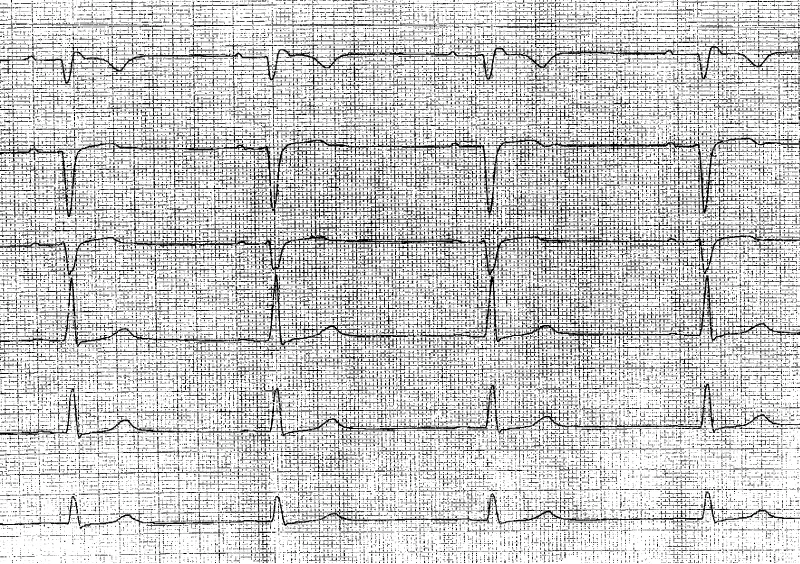

Founder mutations are rare causes in arrhythmogenic cardiomyopathy including TMEM43 und phospholamban mutations. The incidence is approximately 1%. P.S358L TMEM43 mutations cause aggressive, in most cases biventricular arrhythmogenic cardiomyopathy [1], with the necessity of primary prophylactic ICD implantation in men and in women>30 years for sudden cardiac death prevention. The mutation increases the stiffness of the cell nucleus thus producing the massive loss of cardiomyocytes [2]. P.Arg14del phospholamban mutations cause biventricular arrhythmogenic cardiomyopathy with predominant heart failure, and in some cases, secondary sudden cardiac death [3]. Both founder mutations have characteristic electrocardiographic appearance, together with typical ECG manifestations of arrhythmogenic cardiomyopathy like right precordial T-wave inversions, terminal activation delay and epsilon waves in right precordial leads. Typical ECG manifestations in TMEM43 mutations are poor R-wave progression in right precordial leads (Figure 1), often associated with T-wave inversions in lateral leads [4]. Typical ECG manifestations in phospholamban mutations are low voltage ECG [5], more than complete right bundle branch block [6], epsilon waves in right precordial leads and in lead aVR [7] and right precordial T-wave inversions (Figure 2). Atrial fibrillation occurs frequently.

We followed a family with founder p.S358L TMEM43 mutation with sudden cardiac deaths in two sons. Their sister was diagnosed as having arrhythmogenic right ventricular cardiomyopathy in younger<30 years age. The mother was also TMEM43 positive, had no complaints and had no electrocardiographic criteria of arrhythmogenic cardiomyopathy. The ECG of the two sons represented with poor R progression in right precordial leads, coved-type and saddleback type ST segment elevation, retrospectively, and T-wave inversion in lateral leads in one son.

The electrocardiogram of their sister revealed R wave loss in right precordial leads, terminal activation delay, and no signs of T-wave inversions. At the age of >30 years an ICD implantation was performed for primarily prophylactic reasons. The mother remained without any symptoms, and the ECG remained normal.